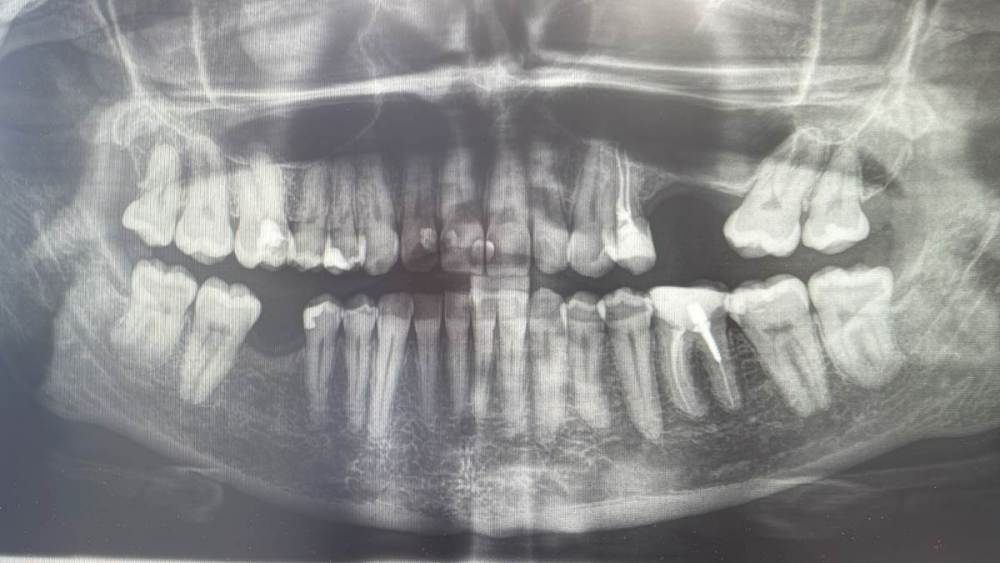

В Вашем случае, ориентируясь на панорамный снимок могу посоветовать:

консультация ортопеда, ортодонта

большая вероятность , что будет необходимость в удалении 1.8,2.8,3.8,4.8

на компьютерной томографии нужно оценить 1.6 ( с терапевтом и ортопедом)

с ортопедом обсудить 2.4, 3.6..

касаемо 2 сегменте (где отсутствуют 2.5, 2.6): необходимо провести синус-лифтинг (наращивание кости) , вернуть зуб 2.7 на своем место, установить 2 имплантата ,

(с хирургом и ортопедом на консультации сразу определиться с величиной коронок на будущие имплантаты- от этого будет зависеть объем наращивания кости, десны)

+ нужно будет установить имплантат 4.6